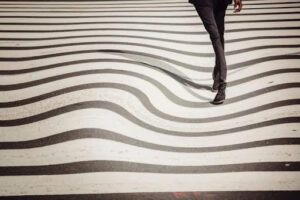

Os sintomas são distorção da visão central associado a um escotoma (mancha) escuro, arredondado e central.